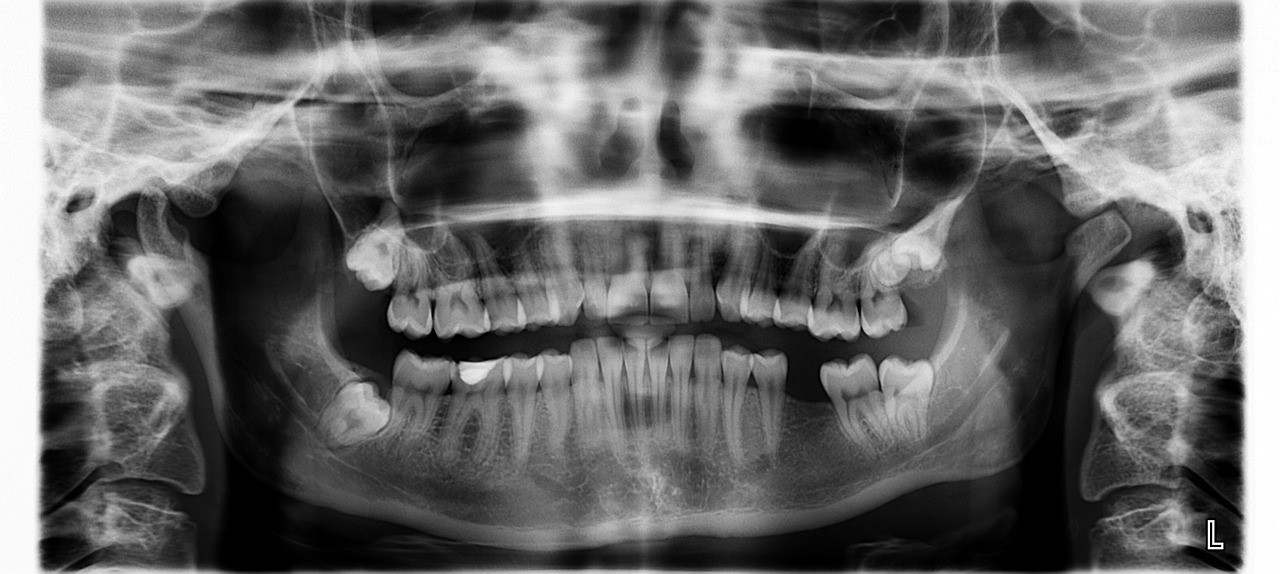

- X-레이 검사 : 치과 전문의는 X-레이 검사를 통해 과잉치아의 존재 여부와 위치, 그리고 주변 치아와의 관계를 정확히 파악할 수 있습니다. 이는 적절한 치료 계획을 세우는 데 중요한 정보를 제공합니다.